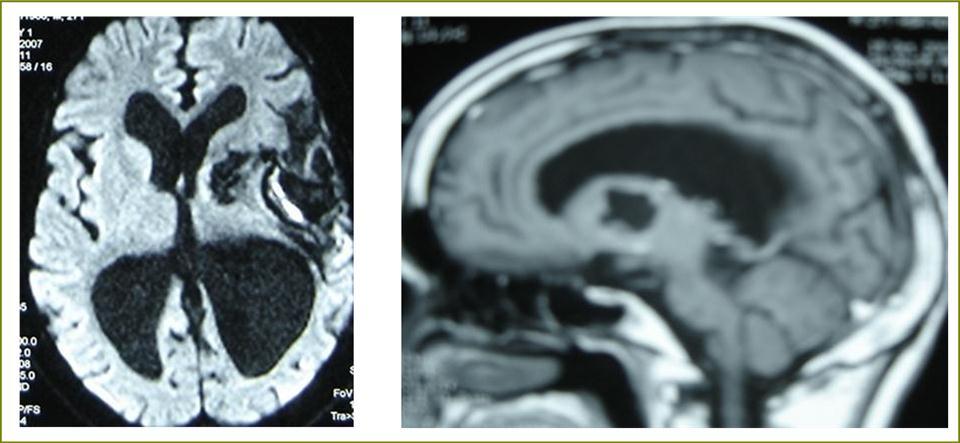

A 27 years-old male patient was admitted with 1 month history of headache, fever, short term memory lack, aphasia, right hemiparesis and seizures. He had liver hydatid cysts excised 8 years before and was treated with adjuvant medication (albendazole). The neurological examination revealed right central third cranial nerve palsy and hemi paresis, with Babinski sign positive, aphasia and papilledema on ocular fundus. The Glasgow Coma Scale was evaluated to 10/15 (E:3; V:1; M:6). A brain CT scan showed a large left temporoparietal intracerebral multiple and calcified hydatid cysts, important mass effect with midline shift about 7 mm following by an obstructive hydrocephalus (Figure 1). Other cysts were found in thalamic region (Figure 2). The Thoraco-abdominal CT scan showed multiple intra peritoneal hydatid cysts (Figure 3). A left temporo parietal craniotomy was performed in emergency. After corticectomy, using Arana-Iniguez technique, the appearance of the capsule suggested infected hydatid cysts with a purulent material which was aspirated. Numerous hydatid cysts were lifted away and several daughter vesicles were carefully removed without rupture (Figure 4). Macroscopically, the abscess wall appeared to be thick, calcified and tightly attached to lateral ventricular, so it could not be removed. The deep cyst overlying the third ventricle was left.in place. Microscopic examination demonstrated live scoleces, protoscoleces and multiple hooks. These findings are consistent with hydatid cyst (granulosis ecchinococcus) (Figure 5). Bacteriology examination found several white blood cells in the pus (neutrophilia) and infection by streptococcus pneumonia. This was consistent with infection. After surgery, the patient had medication (albendazole, specific antibiotherapy and phenobarbital). The inflammation assessment in the blood showed leukocytosis, a high C-reactive protein rate and increased erythrocyte sedimentation rate. Post operative CT scan was performed and showed the residual calcified capsule and decreased ventricular size (Figure 6). Clinical improvement was achieved after treatment. One month after the initial diagnosis, CT scan of the brain showed no recurrence and a physical examination revealed a neurologically intact, fully functional patient and eyes fundus normal. He was discharged and went to abdominal surgery two months later with complete intra abdominal cysts removal. Albendazole treatment was continuing for six months and radiological exploration was performed by brain MRI with spectroscopy at three and six month later. This showed that infection had resolved and the deep cyst overlying the third ventricle is less spherical (Figure 7, Figure 8). Four years later, the outcome was good.

Figure 7.sagittal and axial T1 C+ MRI showing the residual capsule and deep cyst.

Figure 8.sagittal T1 C+ MRI and axial spectroscopy showing the residual capsule and deep cyst which is less spherical.